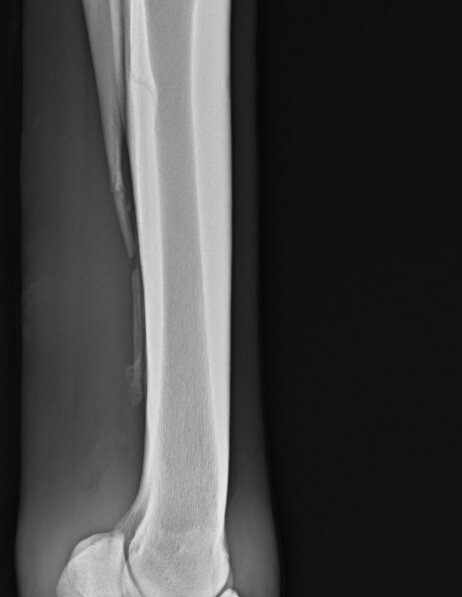

Ibbel schreef:Ik kan me niet voorstellen wat er mis zou kunnen gaan of wat de contra-indicaties van een operatie aan het griffelbeentje zouden kunnen zijn. Gebroken griffelbeentjes genezen niet, het afgebroken deel zal na verloop van tijd wel ingekapseld worden, maar dan heb je een los botfragment onderhuids zitten wat op allerlei structuren kan gaan drukken.

Cowgirl schreef:Ik zou die foto's opsturen naar een goede paardenkliniek en hun een oordeel laten maken.

Het ziet er behoorlijk heftig uit alhoewel ik ooit eens foto's gezien heb van en paard waarbij het gewoon verbrijzeld was..Daar konden ze niks mee, paard zou blijvende schade houden. Dier is dan ook ingeslapen.